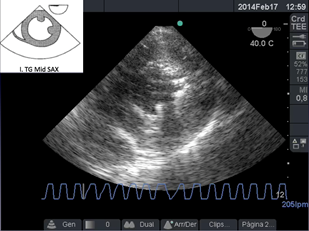

La salida de circulación extracorpórea (CEC) dificultosa es un evento que necesita ser reconocido para instaurar un tratamiento precoz. (Figura a)

Reconocer un ritmo de fibrilación ventricular y actuar desfibrilando de inmediato es el principal objetivo (Figura b), pero a continuación analizar la causa de la fibrilación, por ejemplo el ingreso de aire en la arteria coronaria derecha cuyo tratamiento es aumentar la presión de perfusión coronaria, reingresar a CEC y/o agregar s inotrópicos para aumentar la contractilidad; o una isquemia aguda de dicha arteria que lleva a la necesidad de realizar un puente venoso, tal es el caso de reconocer con ETE el signo de McConnel o signos de aumento de presión de cavidades derechas17. El aire puede ingresar también hacia la arteria pulmonar y observar esta situación a través de ETE nos obliga a informar al cirujano para lograr la completa desairación 18. (Figura cyFigura d)